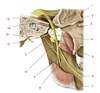

Deep Face (Part I) Flashcards

(242 cards)

A

Zygomatic process (of temporal bone)

B

Tubercle (of temporal bone)

C

Groove for deep temporal vessels (of temporal bone)

D

Postglenoid tubercle (of temporal bone)

E

Supramastoid crest (of temporal bone)

F

Suprameatal spine (of temporal bone)

G

Opening of external acoustic meatus (of temporal bone)

H

Tympanomastoid fissure (of temporal bone)

I

Mastoid process (of temporal bone)

J

Tympanic part (of temporal bone)

K

Vaginal process (of temporal bone)

L

Styloid process (of temporal bone)

M

Angle (of mandible)

N

Ramus (of mandible)

O

Condylar process (head and neck)(of mandible)

P

Mandibular notch and coronoid process (of mandible)

Q

Anterior (surface of maxilla)

R

Infratemporal (surface of maxilla)

S

Zygomatic bone

T

Zygomatic arch

U

Frontal bone

V

Greater wing of sphenoid

W

Squamous part of temporal bone

1

Articular tubercle